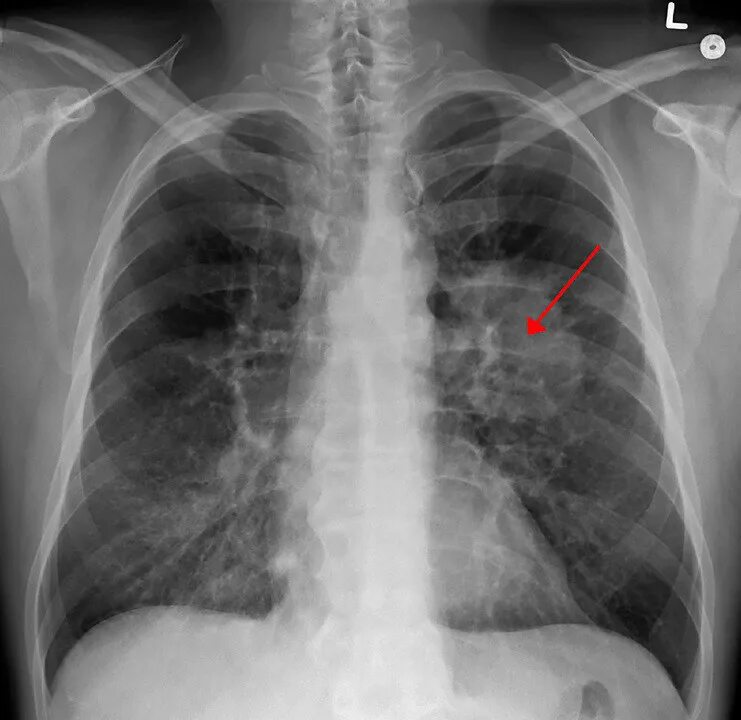

Рак легких 1